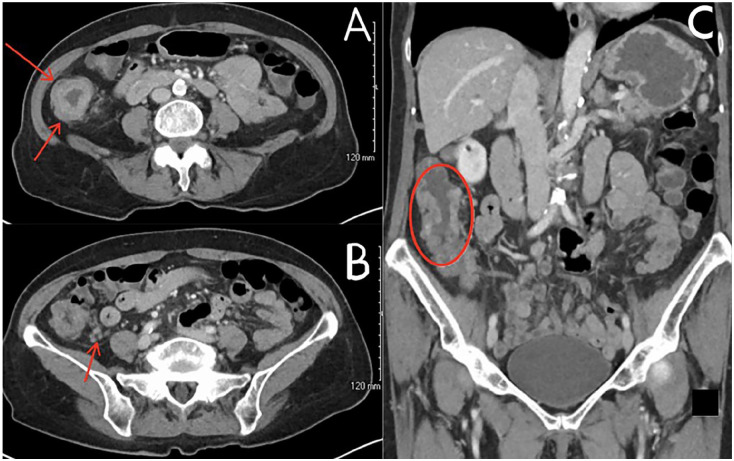

具有错配修复缺陷(dMMR)和微卫星不稳定性高(MSI-H)状态的结直肠癌(CRC)代表了对免疫检查点抑制剂(ICIs)反应良好的高度免疫原性亚群。然而,ICIs在可切除的早期结直肠癌中的作用仍在研究中。我们报告一例81岁的妇女诊断为III期腺癌的右结肠,谁拒绝手术。免疫组化显示MLH1和PMS2缺失,与dMMR一致。肿瘤基因组分析显示MSI-H、高肿瘤突变负担、BRAF V600E和BRCA2突变。种系检测BRCA和Lynch综合征相关突变呈阴性。患者接受新辅助派姆单抗治疗。4个月后,肠系膜淋巴结病变消退,但局灶性结肠增厚持续存在。病人再次拒绝手术。在派姆单抗治疗10个月时,PET/计算机断层扫描和结肠镜检查显示没有残留疾病。她出现了与免疫相关的肾上腺功能不全,用皮质类固醇治疗。该病例显示,在患有体细胞dMMR/MSI-H、BRAF V600E和BRCA2突变的患者中,单抗派姆单抗治疗可切除结肠癌的临床完全缓解。它支持了早期使用icis(在转移进展和免疫逃逸之前)可能提高疗效的假设。该报告强调了在基因选择的结直肠癌患者中,个性化、省去手术的治疗策略的潜力。

Colorectal cancer (CRC) with deficient mismatch repair (dMMR) and microsatellite instability-high (MSI-H) status represents a highly immunogenic subset that responds well to immune checkpoint inhibitors (ICIs). However, the role of ICIs in resectable, early-stage CRC remains under investigation. We report the case of an 81-year-old woman diagnosed with stage III adenocarcinoma of the right colon, who declined surgery. Immunohistochemistry revealed loss of MLH1 and PMS2, consistent with dMMR. Tumor genomic profiling demonstrated MSI-H, high tumor mutational burden, BRAF V600E, and BRCA2 mutation. Germline testing was negative for BRCA and Lynch syndrome-associated mutations. The patient was treated with neoadjuvant pembrolizumab. After 4 months, mesenteric lymphadenopathy resolved, but focal colonic thickening persisted. The patient again declined surgery. At 10 months of pembrolizumab therapy, PET/computed tomography and colonoscopy showed no residual disease. She developed immune-related adrenal insufficiency, managed with corticosteroids. This case demonstrates complete clinical remission of resectable colon cancer with pembrolizumab alone in a patient with somatic dMMR/MSI-H, BRAF V600E, and BRCA2 mutations. It supports the hypothesis that early use of ICIs-prior to metastatic progression and immune escape-may enhance efficacy. This report highlights the potential for personalized, surgery-sparing treatment strategies in genomically selected CRC patients.